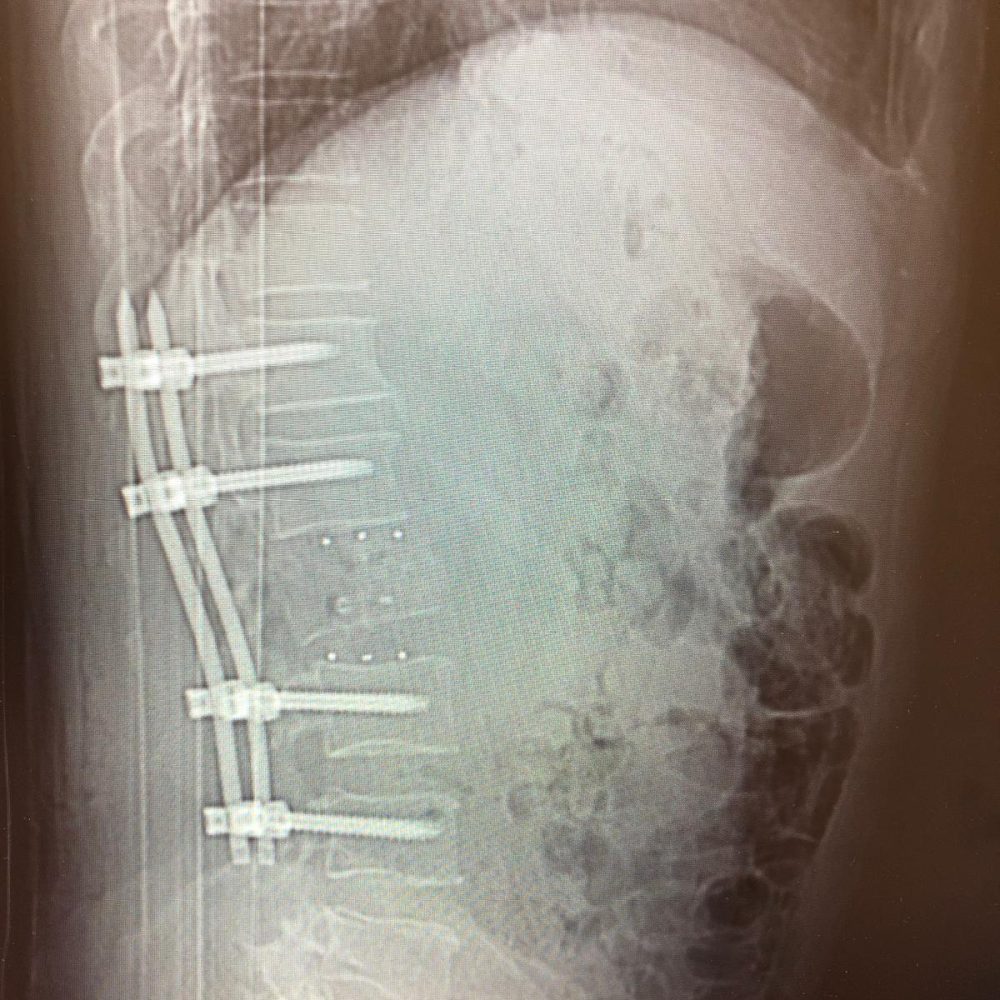

- Leczenie operacyjne wielopoziomowej choroby zwyrodnieniowej ze stenozą kanału kręgowego

- Operacje kręgosłupa z wykorzystaniem robota operacyjnego